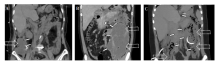

许克东, 马振华, 曹芳, 仵正. 重症急性胰腺炎腹腔不同分区局部并发症的微创治疗[J]. 外科理论与实践, 2022, 27(01): 46-51.

XU Kedong, MA Zhenhua, CAO Fang, WU Zheng. Minimally invasive treatment for local complications of patients with severe acute pancreatitis in different abdominal partitions[J]. Journal of Surgery Concepts & Practice, 2022, 27(01): 46-51.